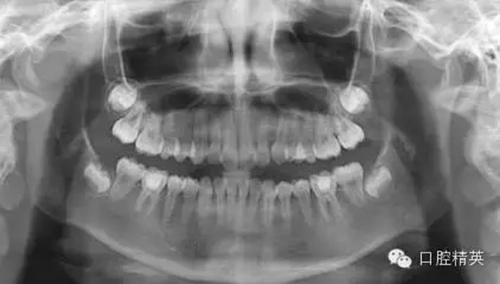

1,術(shù)前X-ray,常規(guī)術(shù)前攝片,為患者和自己保留一份客觀記錄。

3,術(shù)前左下6近中根管斷針X-P,斷針長度約4MM,根尖慢性炎癥影像。。。